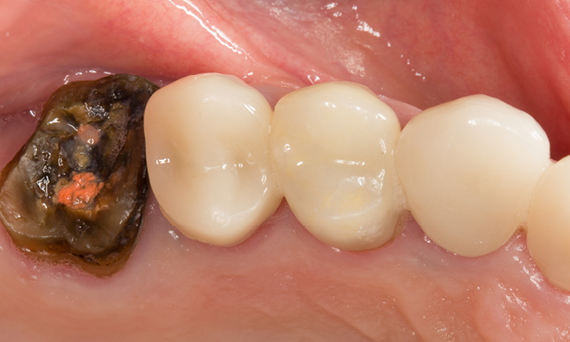

Before

Tooth 26 presenting decay and a failing direct composite restoration.

After

Highly esthetic and functional lithium disilicate ceramic crown.